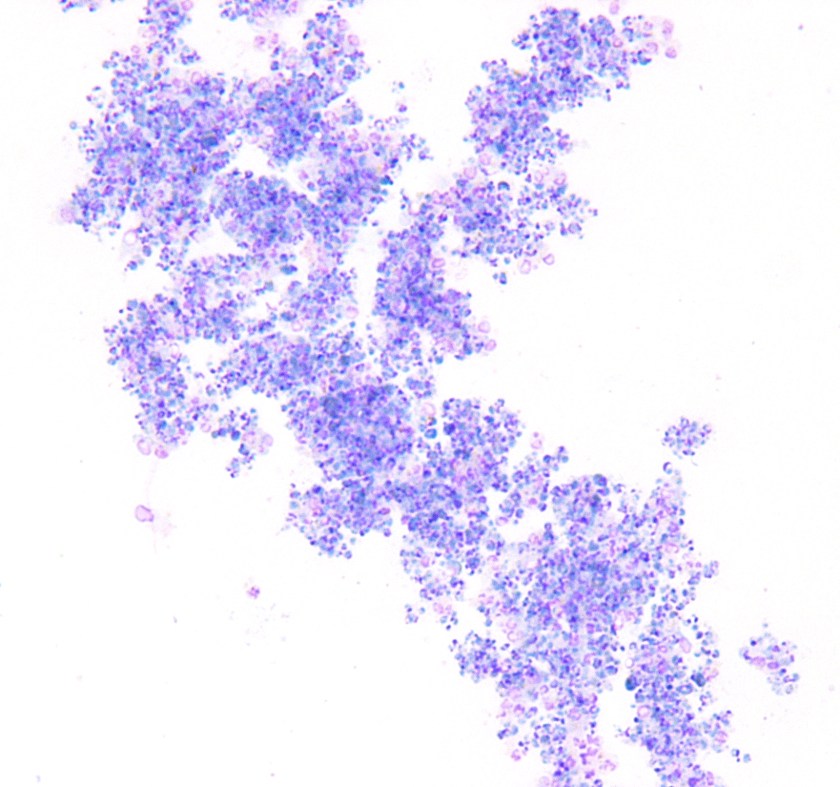

Figure 1. Compilation of several images of Wright Geimsa-stained thin smears of the patient’s peripheral blood, showing numerous and often multiple intra-cellular delicate ring forms, including appliqué forms. Occasional extra-cellular forms were also identified.

Figure 2. Wright Geimsa stain of a thick smear showing numerous aggregated ring forms.

Geimsa-stained thin smears of the patient’s peripheral blood showed numerous infected RBCs and several individual RBCs infected with multiple trophozoites (ring forms). Occasional extra-cellular ring forms were also identified. The rings were small (<1/3 size of RBC) and delicate with 1 or sometimes 2 chromatin dots that give the appearance of headphones. Some of the ring forms were marginalized at the RBC membrane; the so-called appliqué, accollé or marginal forms. Gametocytes were not identified. Parasitemia was calculated to be 10% prior to initiation of treatment. Thick smears showed numerous aggregated ring forms. These features are consistent with Plasmosdium falciparum.